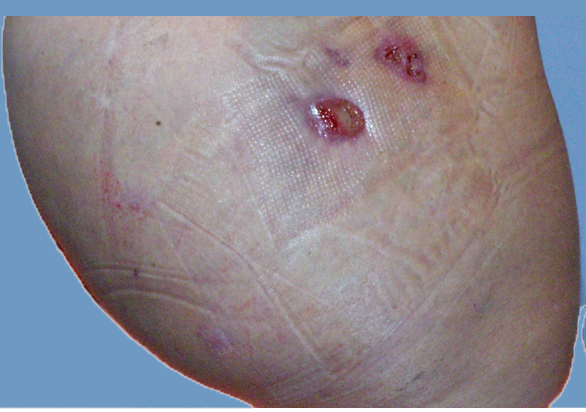

Mesotherapy is ineffective and lead to more ecchymosis than Endopeel .A comparative study shows that with Endopeel you get a great projection of the butts with a lifting too of the infra gluteal fold ( banana fold).

In such case, endopeel is great to perform at least 3 months after fat grafting to get a nice 3d shape.